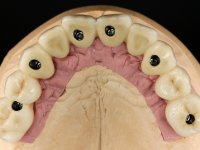

Realizada uma TAC, foi planificada a colocação de 6 implantes no maxilar superior. Foi decidida a colocação de dois implantes na zona dos incisivos centrais, dois implantes na zona dos caninos e dois na zona dos segundos pré-molares. A ausência de estrutura óssea na zona distal do primeiro quadrante implicava a realização de uma regeneração óssea no seio maxilar direito. A cirurgia foi realizada e após a colocação dos implantes foi feita a impressão para confeção de uma prótese provisória metalo-acrílica aparafusada para colocação em carga imediata no dia seguinte. O implante colocado na zona do seio maxilar direito não foi colocado em carga. Passados 6 meses foi realizada a impressão aos 6 implantes com técnica de moldeira aberta e foram confecionados os modelos de trabalho. Numa consulta seguinte foram montados os modelos de trabalho em articulador semi-ajustável utilizando o arco facial e a relação inter-maxilar obtida com a prótese provisória. Foi feita uma muralha de silicone sobre a ponte provisória com o objetivo de orientar o trabalho laboratorial. Realizada a infra estrutura metálica aparafusada esta foi provada em boca e finalmente após colocação de cerâmica o trabalho foi colocado definitivamente. Como passaram vários meses após a realização da primeira TAC foi feita uma segunda para planificar a colocação de implantes no 4º quadrante. Colocaram-se 3 implantes na mesma sessão em que foi feita a extração dos pilares da ponte. Estes implantes foram posteriormente reabilitados com uma ponte metalo-cerâmica aparafusada de três elementos.